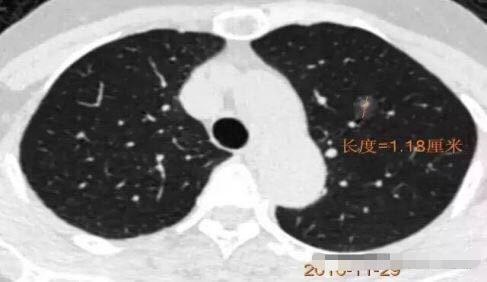

病例4

2013年发现, 每年随访,随访至2016年,病灶逐步增大,2013年5毫米大小,2016年11毫米,3年生长6毫米,平均每年2毫米